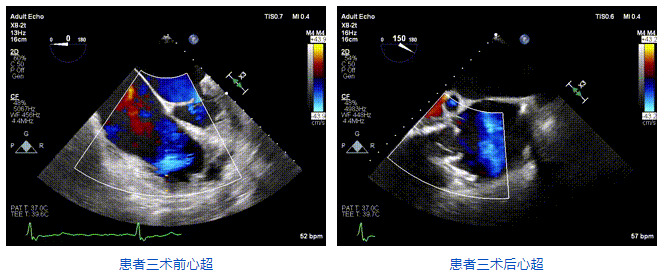

2021年12月24日,復(fù)旦大學(xué)附屬中山醫(yī)院葛均波院士團(tuán)隊成功應(yīng)用LuX-Valve Plus為一例極重度三尖瓣反流(TR)合并房顫、房缺的患者完成了經(jīng)血管三尖瓣置換術(shù),這是在前基礎(chǔ)上,本周完成的第三例經(jīng)血管三尖瓣置換手術(shù),葛均波院士、周達(dá)新教授等與心外科魏來教授、賴顥教授,心超室的潘翠珍教授、李偉教授及麻醉科的郭克芳教授共同完成了本周手術(shù),均獲得圓滿成功!患者術(shù)后超聲顯示無TR,臨床癥狀明顯改善。本周手術(shù)的成功也為LuX-Valve Plus救治性臨床研究添上了濃墨重彩的一筆。

三例患者入院后,葛均波院士團(tuán)隊周達(dá)新教授、潘文志教授、張源博士、陳莎莎博士及心超室的潘翠珍教授、李偉教授對患者的情況進(jìn)行詳細(xì)評估和討論,最終決定為三例患者選擇LuX-Valve Plus40mm、50mm和50mm型號的瓣膜進(jìn)行手術(shù)治療。手術(shù)后即刻拔除氣管插管,術(shù)后患者三尖瓣反流癥狀得到顯著改善,復(fù)查心超結(jié)果顯示人工三尖瓣瓣膜支架固定穩(wěn)定,瓣葉關(guān)閉形態(tài)未見異常,未見明顯反流。